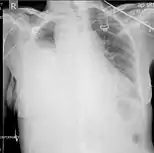

| Chest X-ray showing left sided hemothorax (arrowed) | |

A chest X-ray is the most common technique used to diagnosis a hemothorax.[23] X-rays should ideally be taken in an upright position (an erect chest X-ray), but may be performed with the person lying on their back (supine) if an erect chest X-ray is not feasible. On an erect chest X-ray, a hemothorax is suggested by blunting of the costophrenic angle or partial or complete opacification of the affected half of the thorax. On a supine film the blood tends to layer in the pleural space, but can be appreciated as a haziness of one half of the thorax relative to the other.[5] A small hemothorax may be missed on a chest X-ray as several hundred milliliters of blood can be hidden by the diaphragm and abdominal viscera on an erect film. Supine X-rays are even less sensitive and as much as one liter of blood can be missed on a supine film.[24]